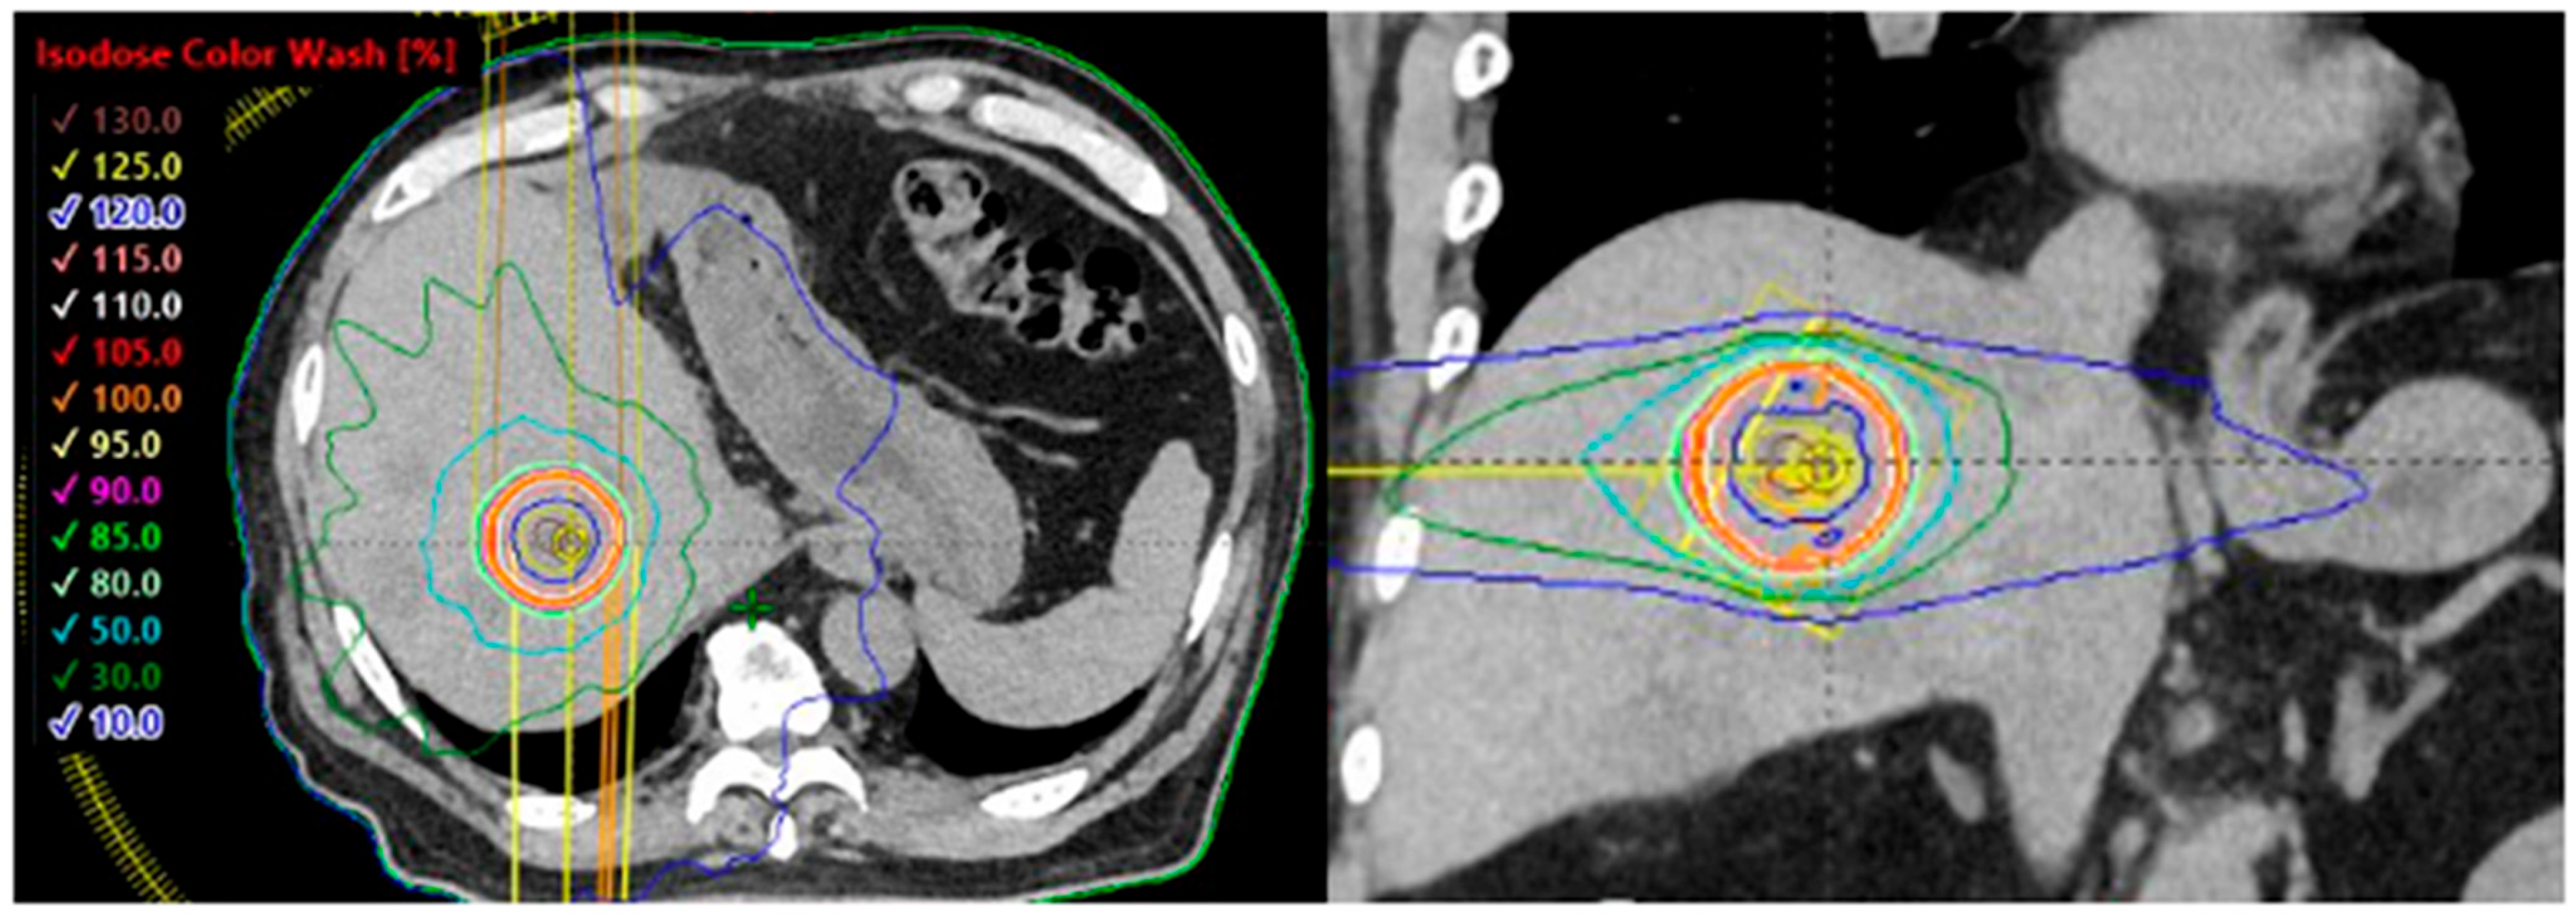

Liver tumors are often difficult to accurately identify using plain computed tomography (CT) alone; therefore, multimodal imaging using contrast-enhanced CT and magnetic resonance imaging (MRI) should be employed for treatment planning. The target should be appropriately defined by fusing planning CT images with those from diagnostic imaging. Liver tumors tend to exhibit greater respiratory motion than lung tumors; therefore, treatment planning should aim to minimize the target size using techniques such as four-dimensional CT and delivery methods like respiratory gating or breath-hold techniques. In addition, dietary restrictions may be required approximately 3 h before treatment owing to gastrointestinal influences. Baseline shifts during irradiation can exceed 1 cm, necessitating appropriate image guidance and adjustments during treatment. The placement of one or more gold fiducial markers on the liver adjacent to the tumor is useful for obtaining accurate positional information during irradiation and for reducing the treatment target, which is essential for motion-tracking irradiation. An example of dose distribution of liver SBRT is shown in Figure 1. Currently, there are no standardized guidelines for the prescribed doses or fractionation schedules in liver SBRT. Appropriate regimens vary depending on tumor size, location, and proximity to organs at risk. Reported SBRT regimens generally involve doses ranging from 25 to 75 Gy in 3–6 fractions. The most commonly used schedule is three fractions [32,33,42], whereas in Japan, 42–48 Gy in four fractions is the most prevalent regimen [43]. Previous prospective and retrospective studies of patients with oligometastatic liver metastases have demonstrated that SBRT can achieve 2-year local control rates of 60–100% (Table 2) [33,34,40,41,42]. The relationship between prescribed dose and tumor control is well established, and several publications recommend delivering a BED (α/β = 10 Gy) ≥ 100 Gy as a threshold for achieving adequate local control [37,40,42]. In a study by Kok et al., the 2-year OS for patients receiving a BED (α/β = 10 Gy) ≤ 100 Gy and >100 Gy were 48% and 85%, respectively [44]. Other studies have used an equivalent dose in 2 Gy fractions >150 Gy as a benchmark [45]. Several prospective studies have also explored single-fraction SBRT [41,46]. Folkert et al. reported excellent local control with single-fraction regimens 35–40 Gy, achieving a 4-year local control rate of 96.6% [44].

Figure 1.

Dose distribution of stereotactic body radiotherapy (SBRT) for liver metastases using volumetric modulated arc therapy (VMAT). The central dose is approximately 130% for a prescription of 40 Gy in five fractions to 95% of the planning target volume (PTV). The red/orange/yellow lines representing the 105%, 100%, and 95% dose lines are concentrated around the PTV contour (red line).